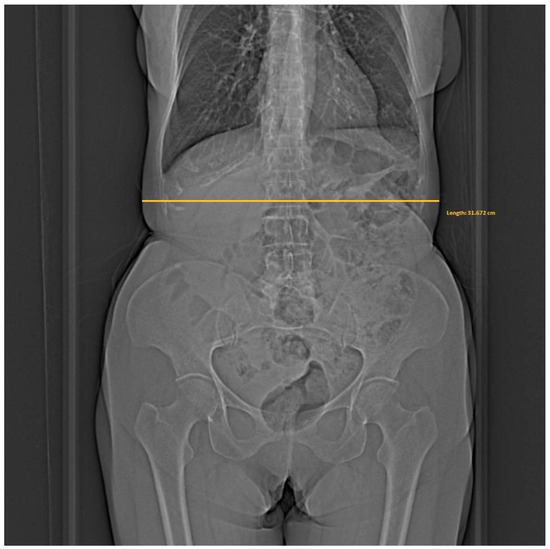

- Whether the patient was in the isocenter—Figure 1 shows the patient outside the isocenter, while Figure 2 shows the patient inside the isocenter.

Figure 1. Image from the Dose&Care system showing patient placement outside the isocenter.

In addition, the widest point in the abdominal area was measured on the patient’s toposcan in the Horos software (4.0.0 RC5). The measurement scheme is shown in Figure 3.

Diagram for measuring the patient’s widest point based on the toposcan performed.